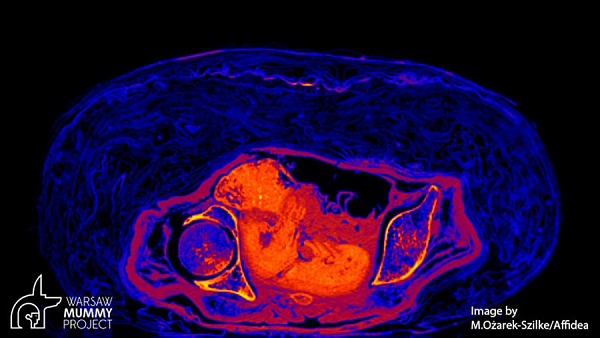

Xác ướp bí ẩn từng bị lầm tưởng là của linh mục Hor-Djehuti cho đến khi kết quả kiểm tra vào năm 2016 cho thấy đó là một phụ nữ. Sau đó vài năm, kết quả quét CT đã gây choáng váng khi người ta phát hiện một bào thai 26-30 tuần tuổi trong bụng cô.

Toàn bộ cơ thể thai nhi trải qua quá trình khoáng hóa, y như cách người Ai Cập đã cố tạo nên cho các mô của xác ướp người lớn. Đó là lý do trong ảnh chụp CT, thai nhi hầu như không thấy xương cho dù hình hài thì rất nguyên vẹn.